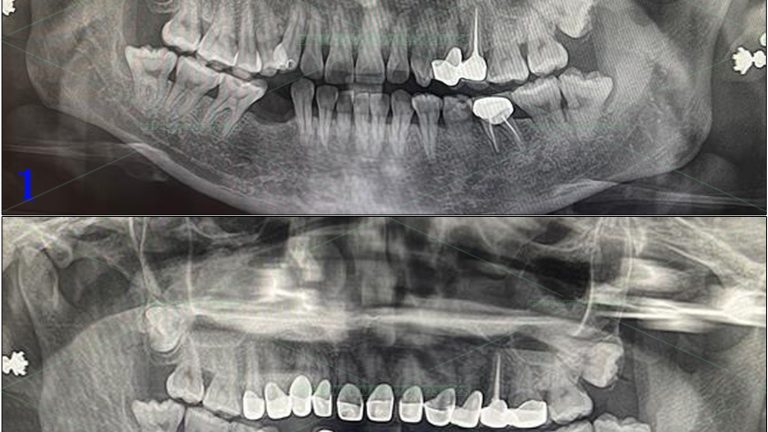

Cô U70 tình trạng vệ sinh răng miệng kém, quá nhiều cao răng gây tiêu xương, lung lay dẫn tới chỉ định nhổ các răng không thể giữ lại được ở hàm dưới và phục hồi lại bằng implant hàm dưới. Kế hoạch điều trị bao gồm vệ cao răng toàn bộ các răng hàm […]